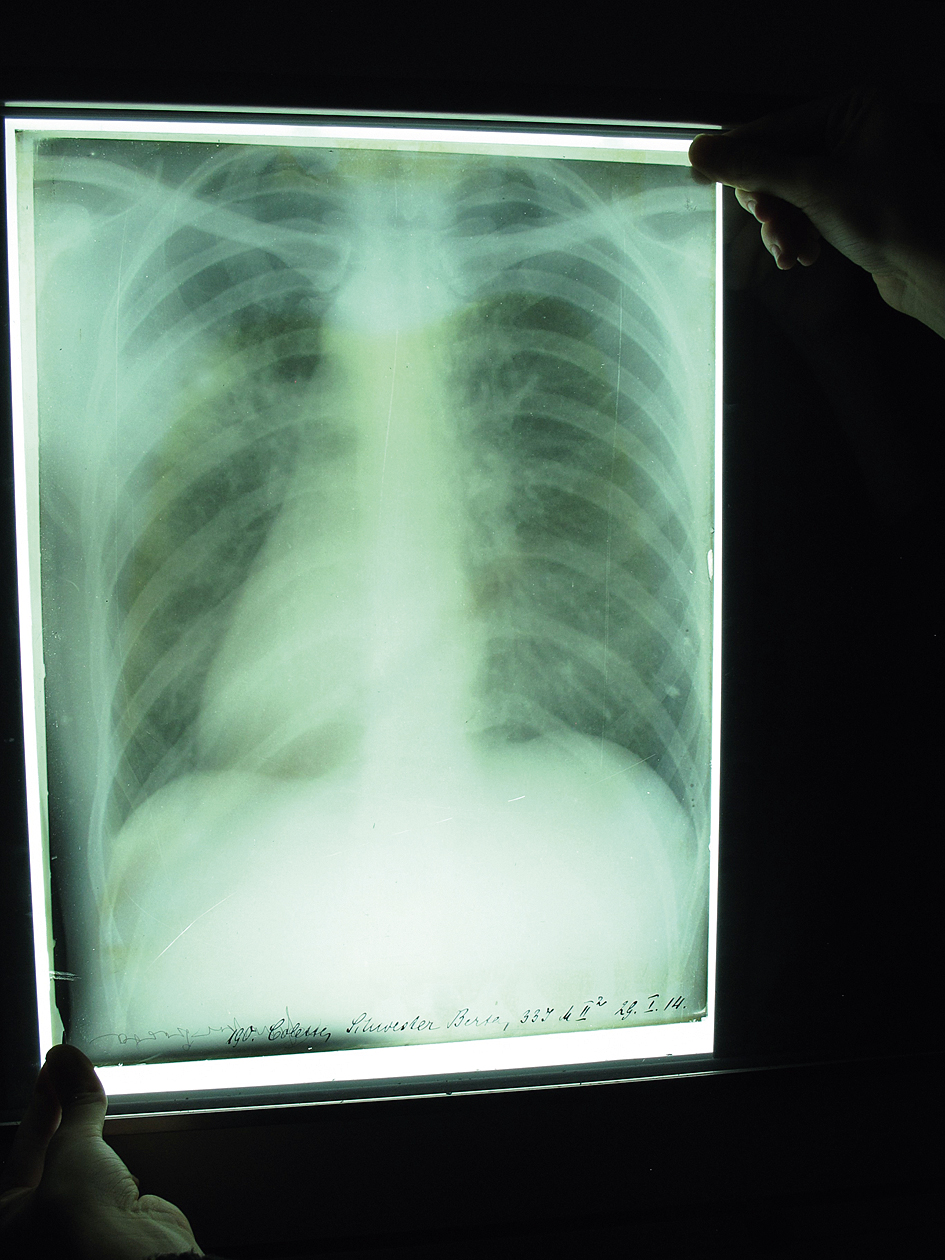

Thorax-Röntgenbild auf einer mit Gelatine-Bromsilber-Lösung beschichteten Glasplatte (1914) | © E. Flom

Ich unterrichte das Lehrfach Strahlentherapeutische Technik an der MTA-Schule am Universitätsklinikum Düsseldorf. Die MTA-Schule hat sich in den vergangenen drei Jahren stark verändert. In allen Klinikbereichen des Universitätsklinikums fehlen MTA-Mitarbeiter/ -innen. Deshalb investiert das Uniklinikum mehr Geld für zusätzliche, neue Lehrerstellen zur Stärkung der Ausbildung. Seit Herbst letzten Jahres werden unter anderem wieder MTA-F (Medizinisch-Technische/r Assistent/-in für Funktionsdiagnostik) ausgebildet. Darüber hinaus wird auch das Schulgebäude saniert, um mehr Unterrichtsräume zu gewinnen. Bei diesen Arbeiten haben wir in einem solchen renovierungsbedürftigen Raum mehrere Kartons entdeckt – augenscheinlich normale Kartons von Röntgenfilmen. Überraschenderweise enthielten diese Kartons uralte, mit Gelatine-Bromsilber-Lösung beschichtete Glasplatten mit Röntgenaufnahmen. „Röntgenphotographien“ – so hat man diese Bilder vor 100 Jahren genannt. Es handelt sich dabei um mehr als 50 Glasplatten, überwiegend 30 x 24 cm2 groß, mit dem Aufnahmedatum, Namen und Alter des Patienten. Die Bilder auf den Röntgenplatten sind zwischen 1909 und 1921 entstanden und zeigen überwiegend Darstellungen des Thorax-(Brustkorb-)Bereiches. Auch die ehemalige, pensionierte Schuldirektorin Monika Schmidt kannte auf Nachfrage den Ursprung dieser Bildplatten nicht. Dabei ist die Schule selbst schon circa 60 Jahre alt.

Ach, Entschuldigung! Es waren damals noch keine MTA. Sie wurden „Röntgenschwestern“, „Spezialschwestern“, „Röntgenassistenten“ genannt – diese Berufsbezeichnung war damals üblich. Wir haben die Platten zuerst katalogisiert und dank Prof. Dr. med. Gerald Antoch, Direktor des Instituts für Diagnostische und Interventionelle Radiologie und in seiner fachlichen Zuständigkeit, auch Ärztlicher Leiter der MTA-Schule, befunden können. Das waren zwei wertvolle Unterrichtsstunden von Prof. Antoch unter der aktiven Mitarbeit von Schülern/-innen, nicht zu vergessen die hervorragende Arbeit von denjenigen, die diese Röntgenaufnahmen angefertigt haben. Gemeint ist hier die ausgezeichnete Qualität dieser Aufnahmen, die auch selbst nach 100 bis 110 Jahren noch sehr gut ist! Und wie zu erwarten, war es keine Überraschung, dass dabei als Befund die Tuberkulose als Krankheitsursache auf den Bildern diagnostiziert wurde – die typische Erkrankung der damaligen Zeit.